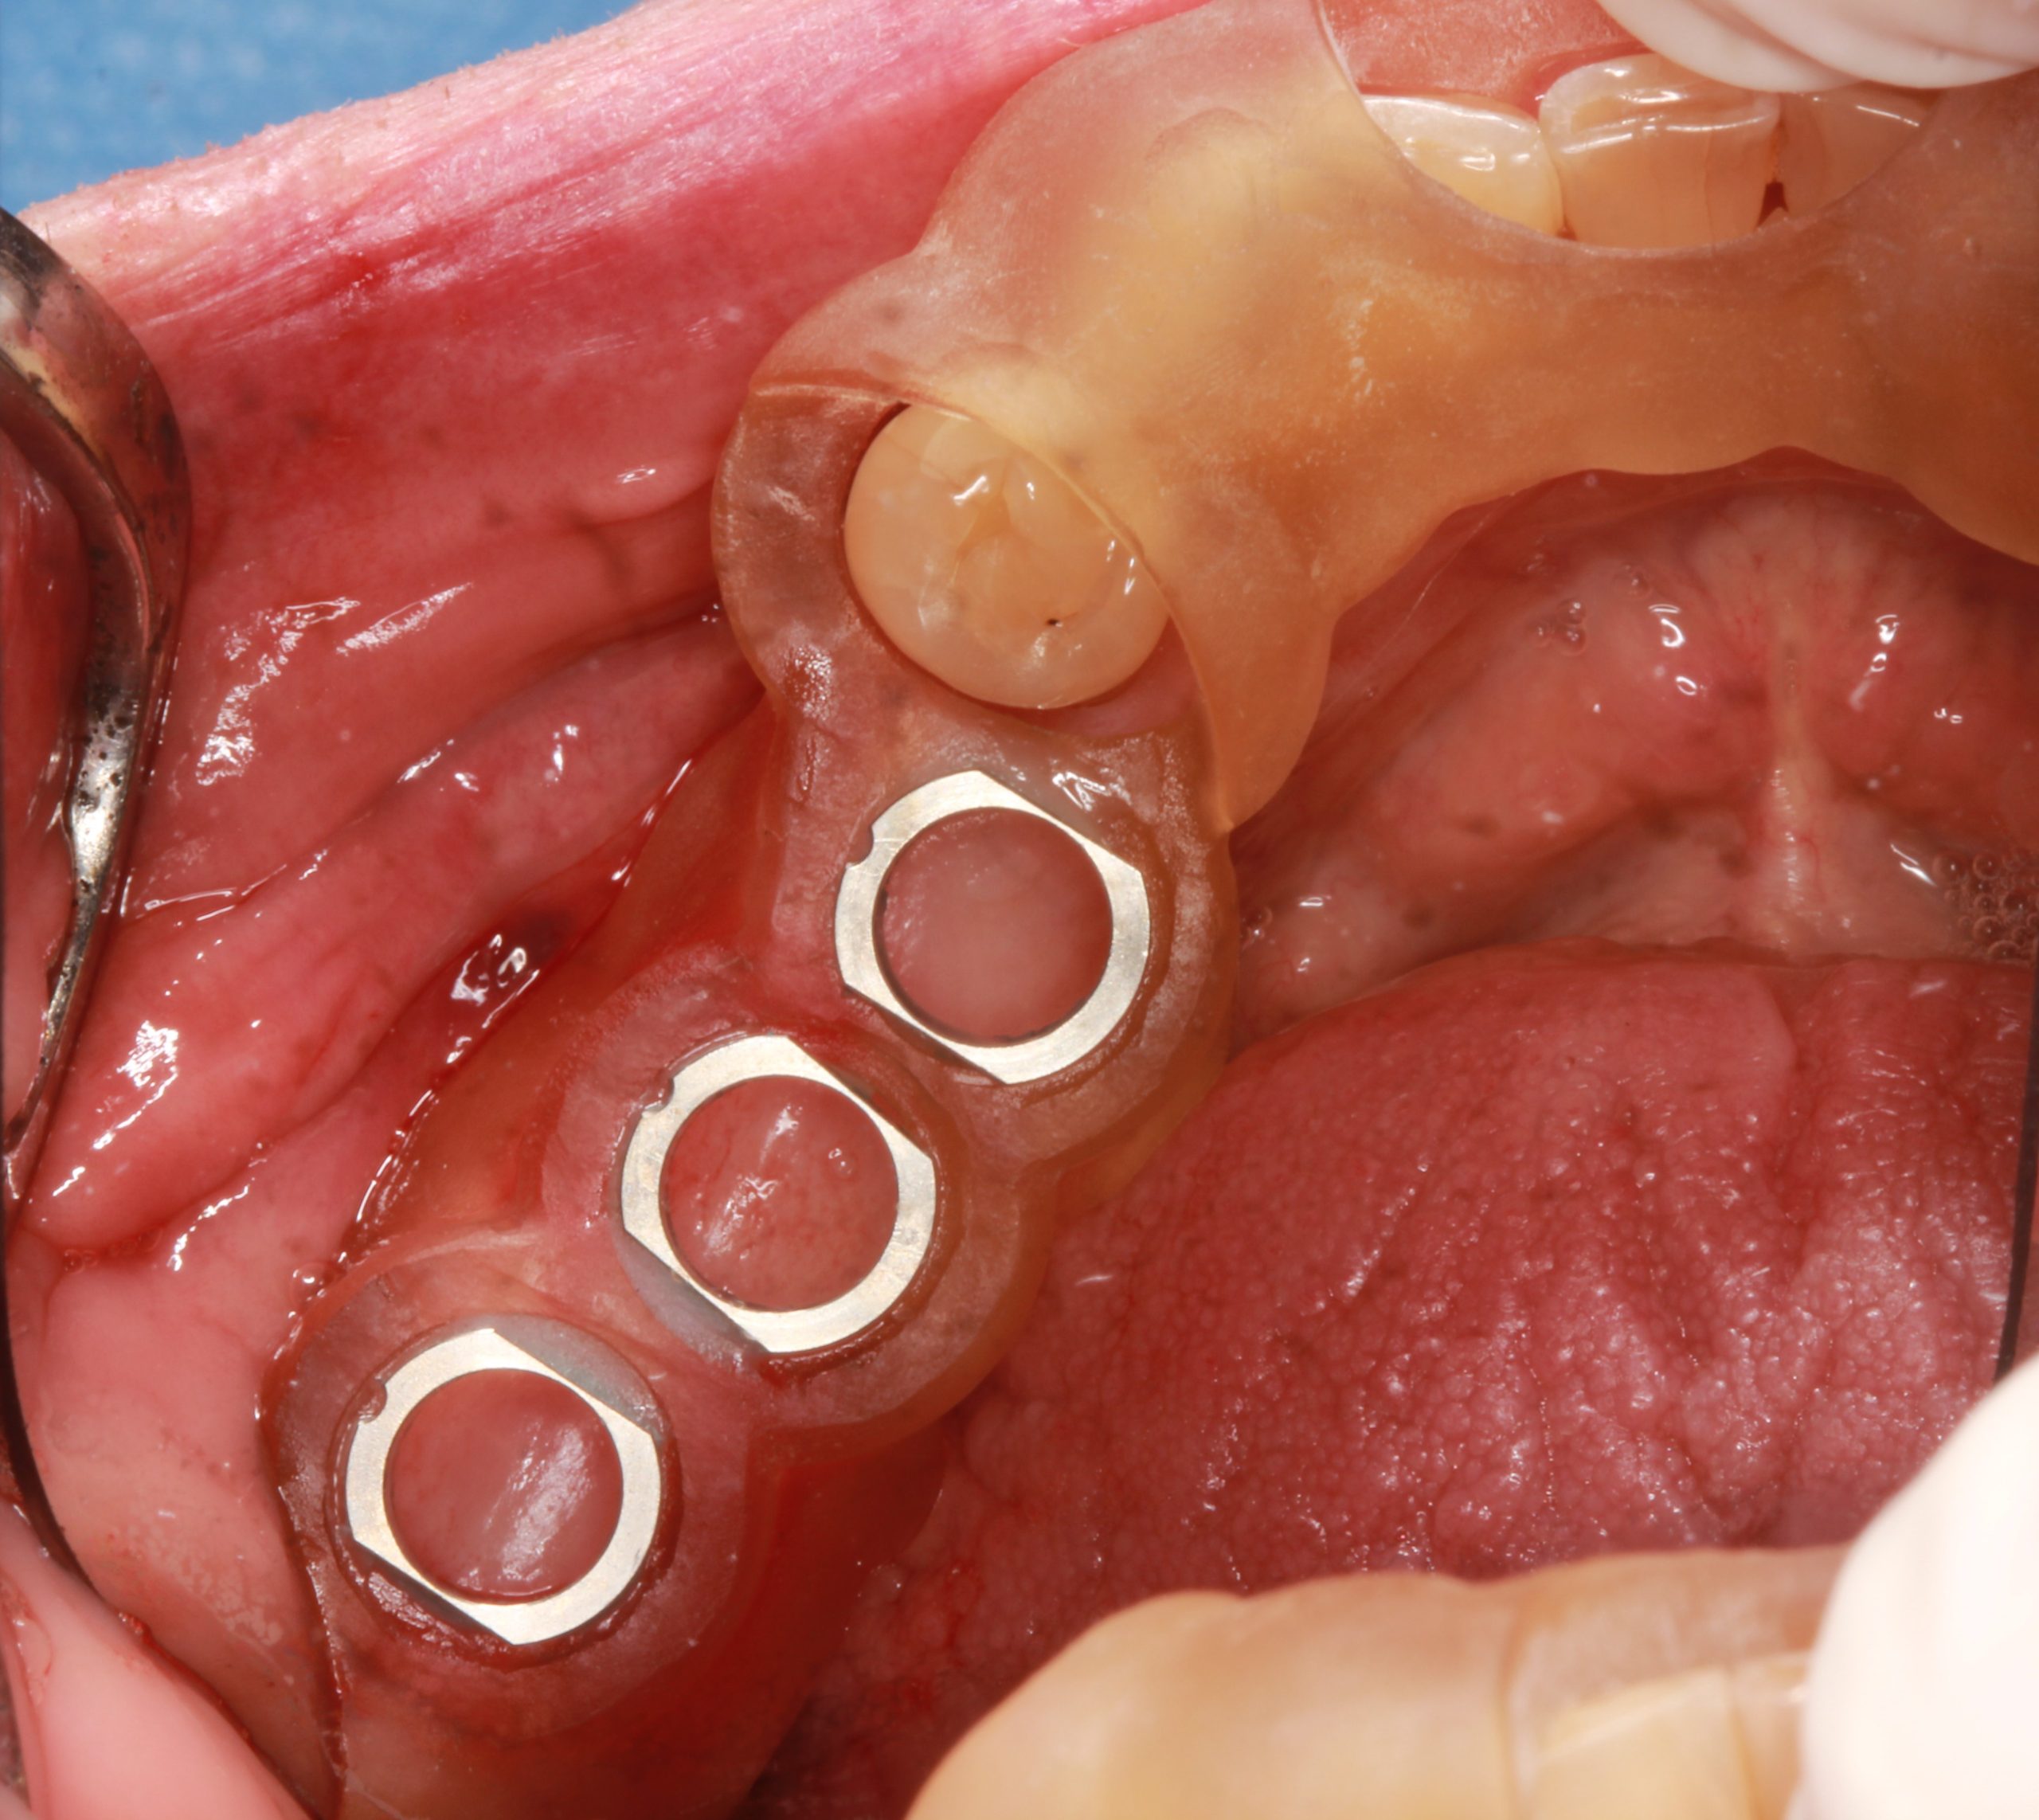

Nach einer Probe des exakten Sitzes der zahngestützten Chirurgieschablone im Mund wurden die Implantate in die geplanten Positionen eingesetzt.

Nach drei Monaten wurden die Implantate freigelegt und der Abdruck gemacht.